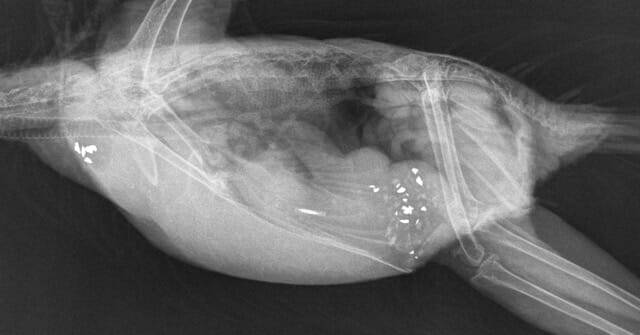

Conscious radiographs usually result in superimposed anatomy and non-diagnostic radiographs. There are times in which conscious radiographs can be indicated, such as in collapsed and debilitated patients when trying to rule in or out certain diagnoses, for example egg binding (Figure 1) or the presence of heavy metals. Routine or planned radiographs should be performed after a small period of starvation – enough to allow the crop to empty and decrease the risk of regurgitation and subsequent aspiration.